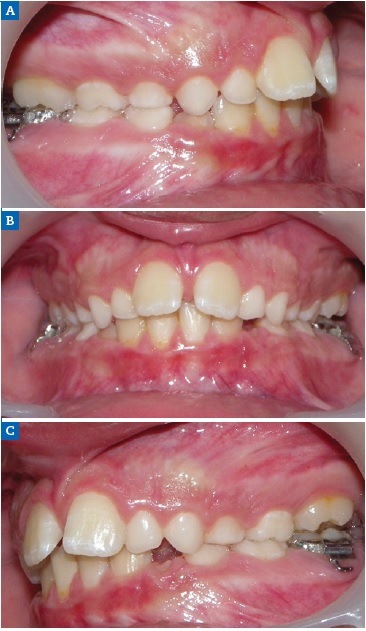

Figure 2 Case 1: Intraoral views of the (A) right, (B) frontal, and (C) left aspects before orthodontic treatment.

An 11-year-old female patient (Figure 1) presented with bilateral MLIA and a 2-mm midline diastema. An intraoral examination revealed healthy dentition and no symptoms or signs of periodontal disease (Figure 2). A panoramic radiograph showed the absence of both maxillary lateral incisors, mesial eruption of the canines, and the presence of deciduous maxillary canines and deciduous right maxillary lateral incisors (Figure 3).